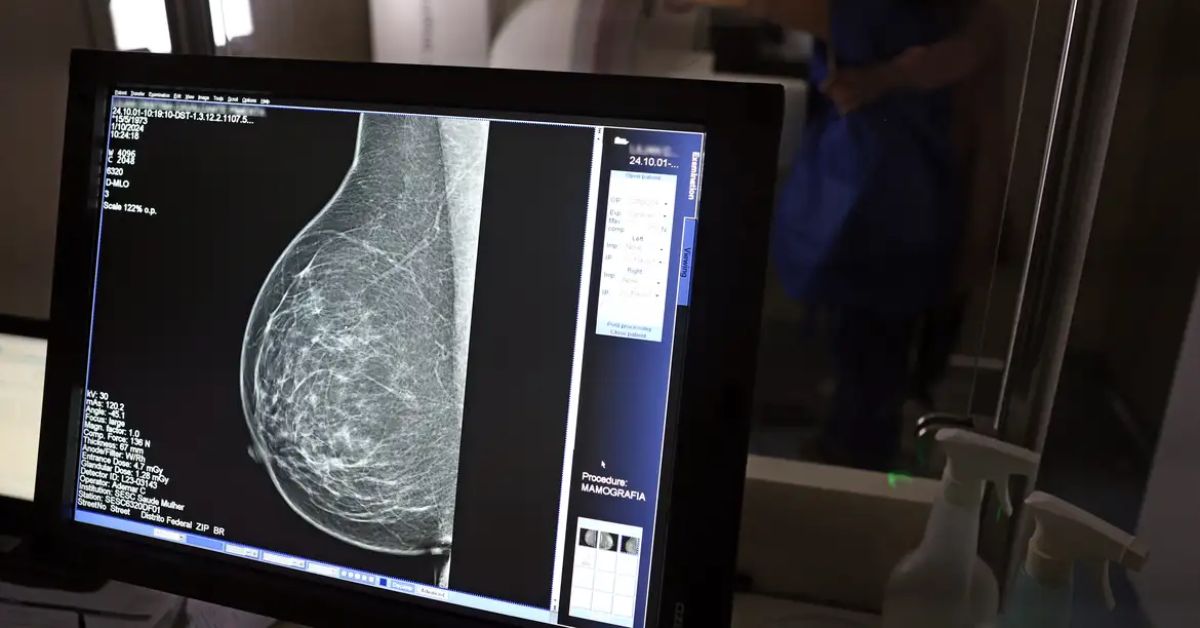

No Outubro Rosa, o Instituto Nacional de Câncer (Inca) estimou 73.610 novos casos este ano no país. É o câncer que mais mata mulheres no Brasil. As mulheres em tratamento pela doença têm o direito de receber o auxílio-doença ou o benefício de prestação continuada.

A vice-presidente da Comissão de Previdência Social Pública da Ordem dos Advogados do Brasil do Rio de Janeiro (OAB-RJ), Danielle Guimarães, destaca que o câncer de mama é uma das doenças que mais afetam mulheres no Brasil, impactando não apenas a saúde física e emocional, mas também a capacidade de trabalho e a segurança financeira das pacientes.